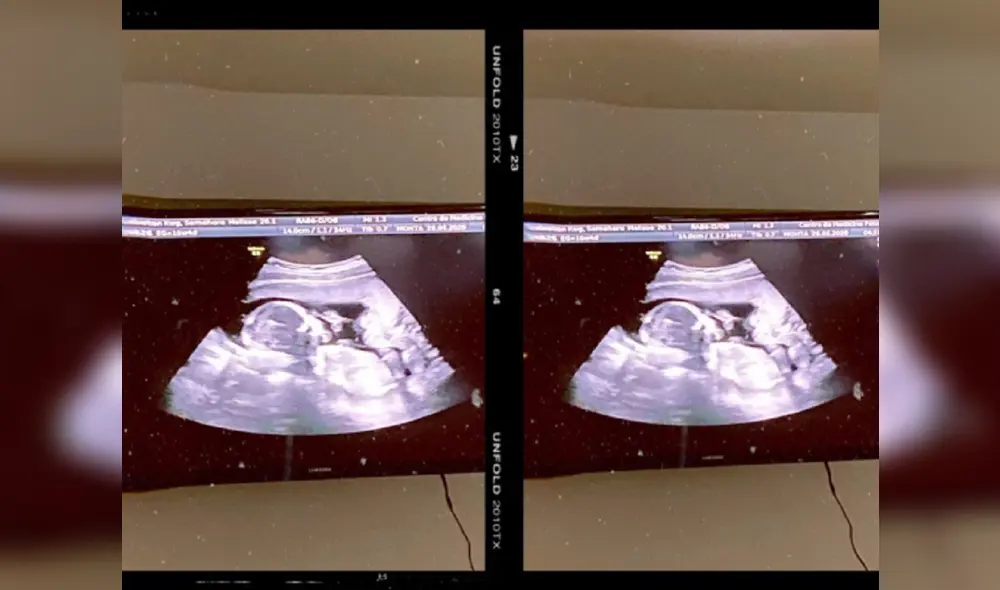

Una pareja de Los Ángeles, Estados Unidos, presentó este lunes 8 de noviembre una denuncia contra una clínica especializada en fecundación in vitro (FIV) tras darse cuenta de que se intercambiaron dos óvulos fecundados y que tuvieron la hija de otra familia.

Cuando Daphna y Alexander Cardinale vieron por primera vez a su bebé recién nacida, en septiembre de 2019, inmediatamente notaron que la niña tenía la piel y el cabello más oscuros que el resto de la familia, contaron sus abogados.

“Las pruebas genéticas revelaron que la bebé que Alexander y Daphna habían dado a luz y criado durante varios meses no tenía relación genética con ellos. Su bebé era la hija biológica de completos desconocidos”, añadió la firma Peiffer Wolf.

Según la demanda presentada este lunes en un tribunal de Los Ángeles, se intercambiaron embriones de dos parejas no relacionadas, presuntamente por negligencia.

La FIV consiste en la inseminación en el laboratorio de un óvulo con un espermatozoide. Posteriormente es reimplantado el óvulo fecundado en el útero de la madre. El proceso lo utilizan a menudo las parejas que tienen dificultades para concebir y también puede incluir la donación de un óvulo, esperma o ambos.